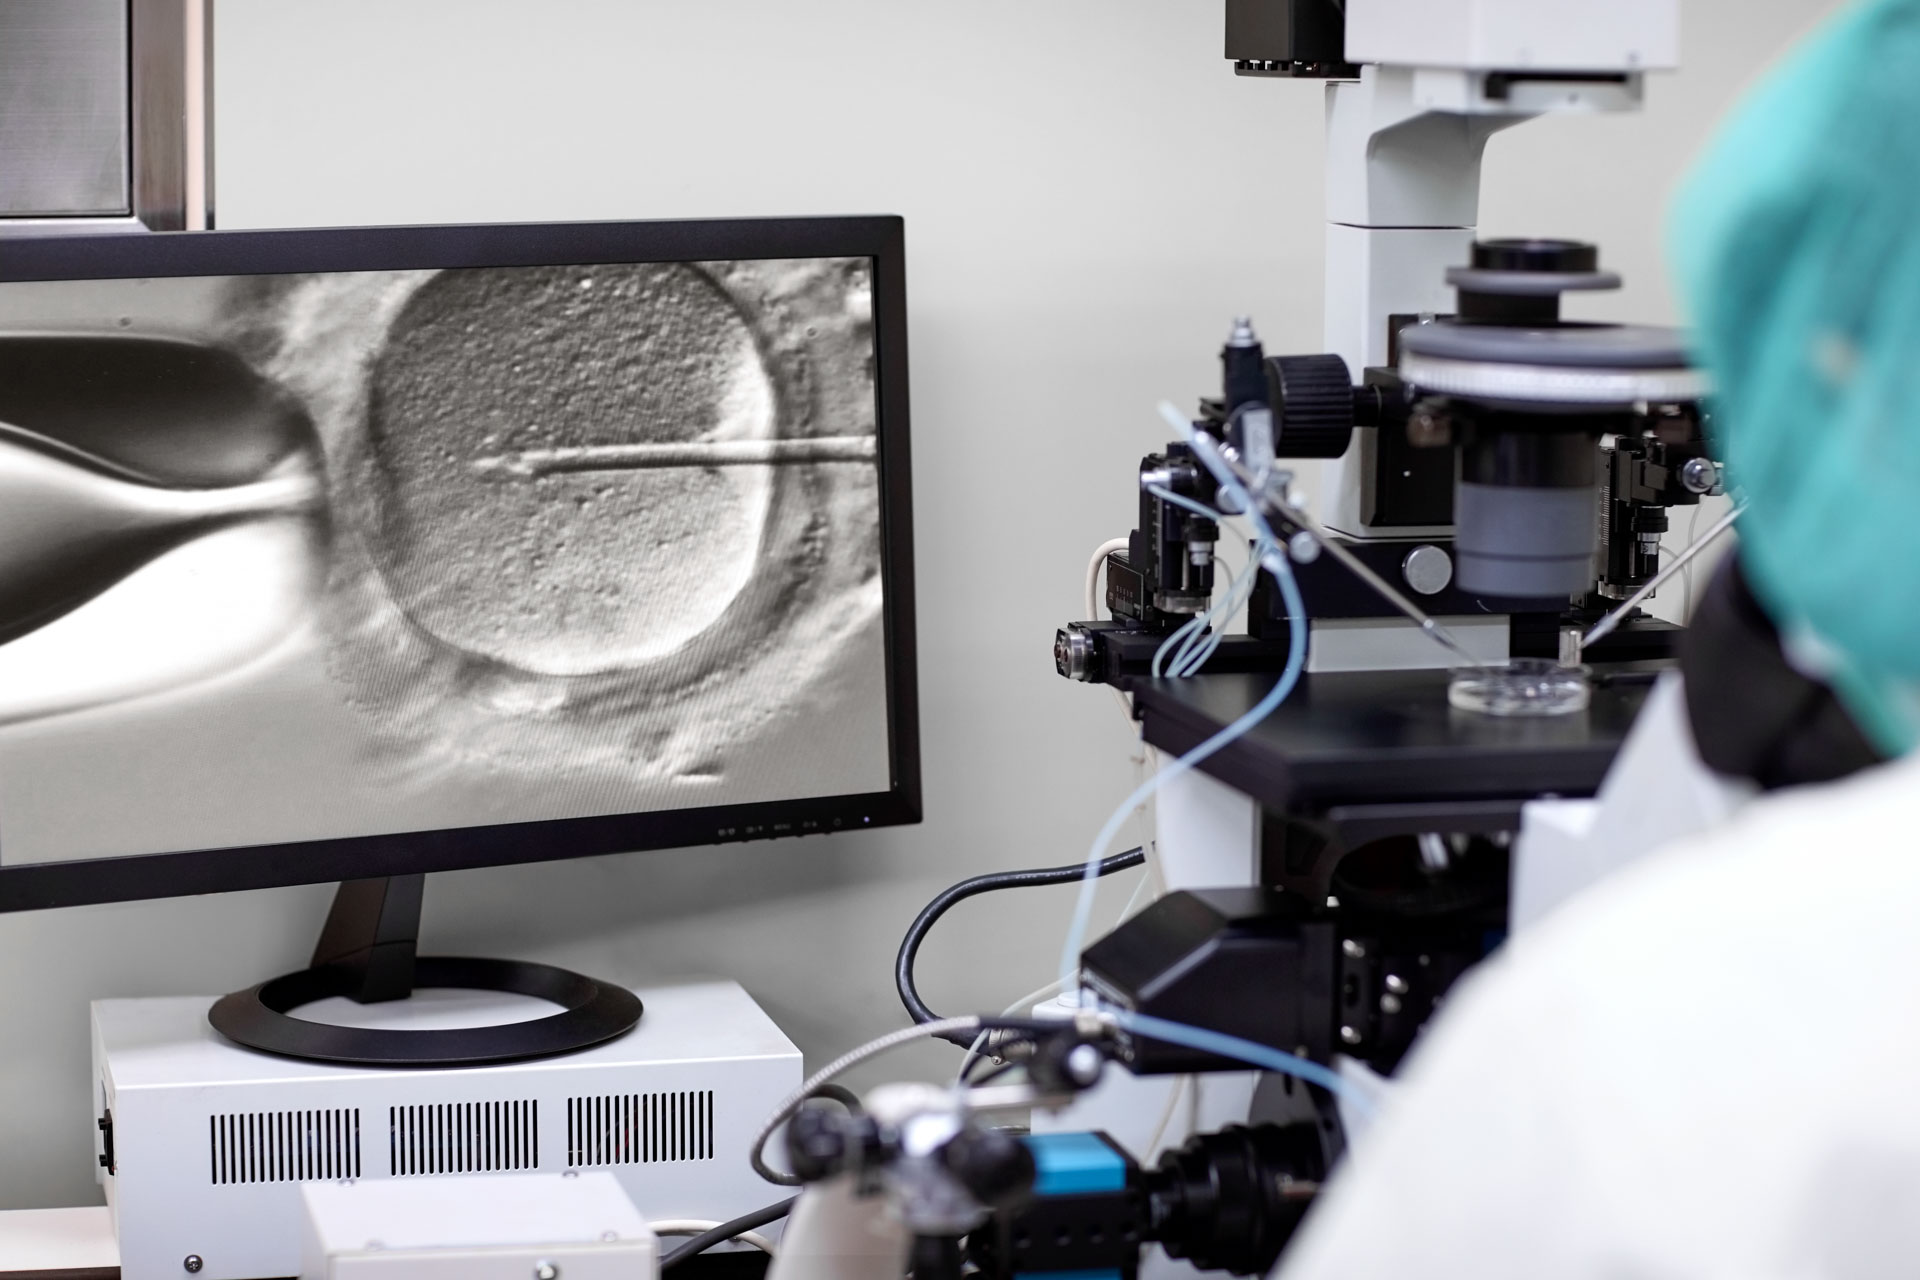

Loans for IVF & fertility treatments

The journey to conceive can be stressful. Prosper takes the worry out of financing fertility medications and procedures.